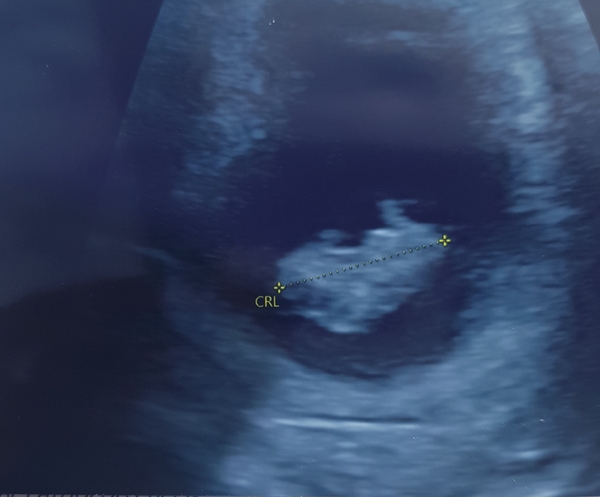

The little bean measured 2.2cm today and we saw a very rapid heartbeat. I have attached a pic

I meant 2.10 cm not 2.2 cm

Olivia2019 lovely scan photo it’s the best feeling ever seeing the heartbeat isn’t it